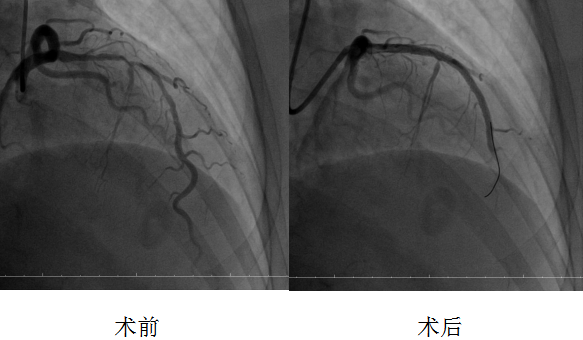

10月17日,在介入科的全力配合下,刘波主任主导开展手术。手术团队运用直径仅1.5毫米的高速旋磨头,以每分钟15万转的转速精准“打磨”血管内钙化病灶,三次旋磨成功打通病变通路,随后顺利为患者串联植入两枚药物支架并以球囊行后扩张。为确保手术效果,团队还通过血管内超声检查精准评估支架贴壁情况,对支架近端进行补充后扩张。复查造影显示,支架释放满意,血管狭窄解除,血流恢复正常。术后1小时即实施双泵透析,有效降低造影剂对肾脏的影响,保障了患者心肾功能稳定。经过后续规范治疗,患者恢复良好,现已顺利出院。